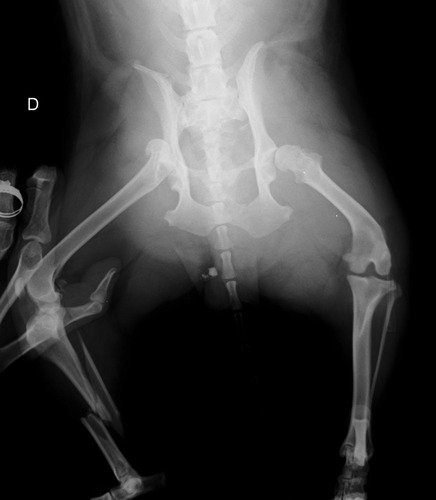

Me chamo João Pedro e sou tutor da cadelinha Filomena. Ela foi atropelada enquanto passeava no dia 11/09 e o responsável fugiu do local. Ela está internada no hospital veterinário e passará por duas cirurgias pois teve fratura de tíbia e fêmur. O total de custo está em torno de R$ 5 mil reais. Será realizado uma rifa com os participantes da vakinha no valor de R$ 300 reais. A cada ajuda será disponibilizado um número para o sorteio, fique a vontade de quanto quiser ajudar.